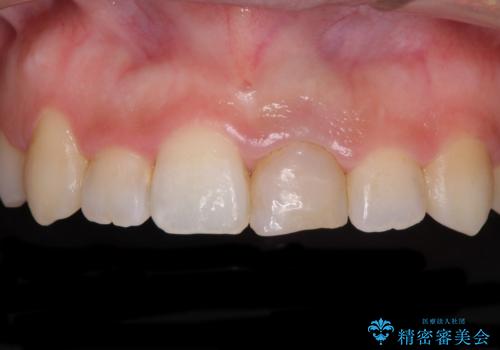

前歯のクロスバイトと変色した歯 ワイヤー矯正とセラミック治療

- 前歯のクロスバイトと神経を取り除いた後に変色してしまった前歯を気にして来院された患者様です。

ワイヤー矯正により矯正治療を行った後に、前歯の補綴治療を行うこととしました。

変色してしまった前歯は、反対側の歯と比べて歯肉が覆い被さっていたため、骨整形を含めた歯周外科処置を行い、歯肉ラインを整えることとしました。

歯周外科処置を行うかどうかは非常に悩んでいらっしゃいましたが、範囲がそれほど広くないため術後の痛みも強くないだろうということで、処置を行うこととなりました。